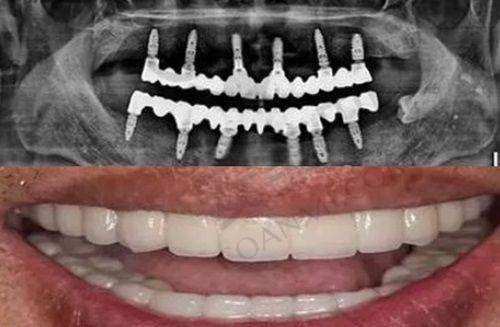

抚州英伦口腔医院的单颗牙种植牙技术有特别多特色。首先,他们采用的是精良的种植系统,这种种植体具有良好的生物相容性,能够与牙槽骨更好地结合,提高种植牙的稳定性和成功几率。其次,医院的医生会根据患者的口腔情况和面部特征,为患者选择更合适的种植体和牙冠,确保种植牙的外观和功能都能达到至佳成效。另外,医院还采用了数字化种植技术,通过口腔CT等设备获取患者口腔的三维数据,医生可以在电脑上进行模拟种植,提前规划种植体的位置和角度,使手术更加精细、安心。这种技术不仅可以缩短手术时间,还能减少患者的痛苦和创伤。

手术后的几天里,我的口腔有一些轻微的肿胀和疼痛,这是正常的术后反应。我按照医生的嘱咐,按时服用消炎药和止痛药,并用漱口水保持口腔清洁。饮食方面,我选择了一些软烂、易消化的食物,避免食用实力强、过烫的食物。大概过了一周左右,肿胀和疼痛就基本消失了。在接下来的几个月里,种植体与牙槽骨逐渐愈合。医生会定期对我进行复查,观察种植体的愈合情况。每次复查时,医生都会详细地跟我讲解我的修复情况,并给予我一些建议和指导。经过几个月的修复,种植体已经完全与牙槽骨结合,医生为我安装了牙冠。安装牙冠后,我感觉种植牙就像自己的真牙一样,外观自然美观,咀嚼功能也修复得良好。

现在,我的单颗牙种植牙已经完成一段时间了,成效真的让我非常满意。种植牙的外观和自然牙几乎没有区别,颜色和形状都特别协调,别人根本看不出来我做了种植牙。而且,种植牙的咀嚼功能也非常好,我可以像以前一样正常吃东西,再也不用担心牙齿缺失带来的不便了。在整个就诊过程中,我感受到了抚州英伦口腔医院医护人员的专精和负责。他们不仅技术不错,而且态度和蔼可亲,让我在就诊过程中感受到了温暖和关怀。我真的非常感谢抚州英伦口腔医院的医生和护士们,是他们让我重新拥有了健康美丽的牙齿。